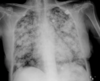

Hemorragia pulmonar bilateral. Aunque la placa de tórax puede resultar útil para el diagnóstico de hemorragia pulmonar, el contexto clínico es fundamental ya que los hallazgos radiológicos son indistinguibles del edema alveolar o de la neumonía. Las radiografías seriadas obtenidas durante varios días tras el episodio de hemorragia pulmonar aguda muestran un cambio de patrón progresivo: los primeros días se observan densidades alveolares difusas con broncograma aéreo de predominio bibasal o perihiliar. La resolución es rápida, mostrando un patrón reticular a los 2 o 3 días que va disminuyendo gradualmente hasta que la radiografía se normaliza por completo en torno a las 2 semanas.